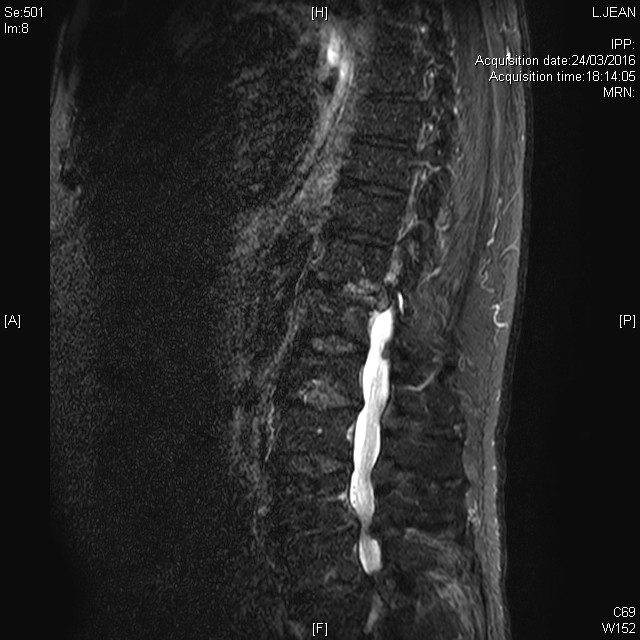

Multiples lésions vertébrales rachidiennes avec compression médullaire et épidurite à l'étage T5, dans le cadre d'un cancer pulmonaire, en séquence T2 STIR

Plasmocytome solitaire du rachis dorsal découvert dans le cadre du bilan d'une fracture vertébrale dorsale spontanée